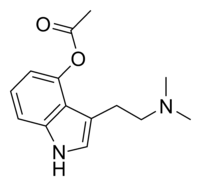

| 4-AcO-DMT | artificial | 4-OCOCH3 | CH3 | CH3 | 4-acetoxy-N,N-dimethyltryptamine | 92292-84-7 |